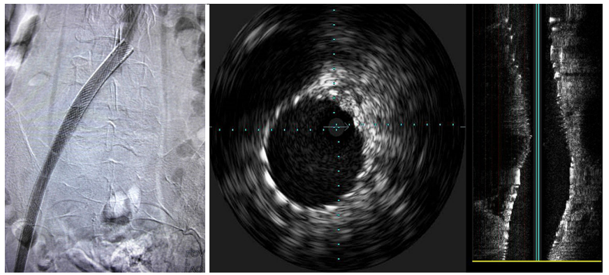

Hình 2: Chụp tĩnh mạch xâm lấn sau đặt stent2

Hình ảnh cho thấy tái thông hoàn toàn tĩnh mạch chậu chung trái; IVUS xác nhận tái thông lòng mạch và stent áp sát tốt.